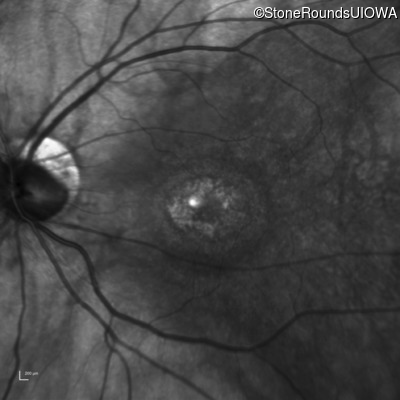

This 52 year old man had normal vision until his mid 30's when he began to have trouble distinguishing colors. the issuing 10 years he had a gradual loss of visual acuity accompanied by increasing photophobia.

| Age at visit: 61 years |

| Age at visit: 64 years |